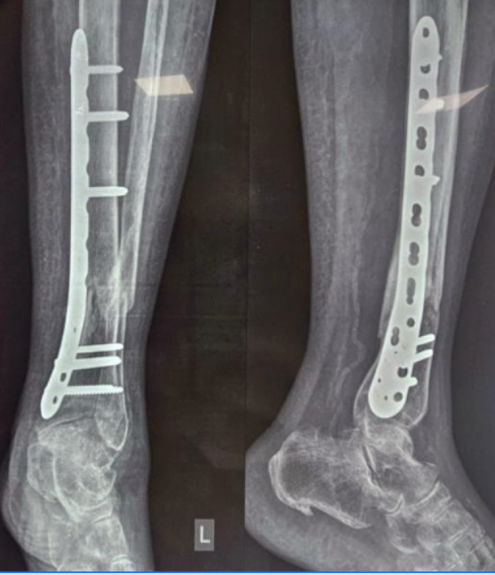

Clinical and Functional Outcome of Distal Tibial Fractures Treated with Minimally Invasive Percutaneous Plate Osteosynthesis Technique using Anatomical Distal Tibial Plate: A Case Series

H Rohit Karthik , Venkata Kiran Pillella , Hemanth Raj , Madhukar Chegu , Vijay Narasimman Reddy , G Puguzhendhi